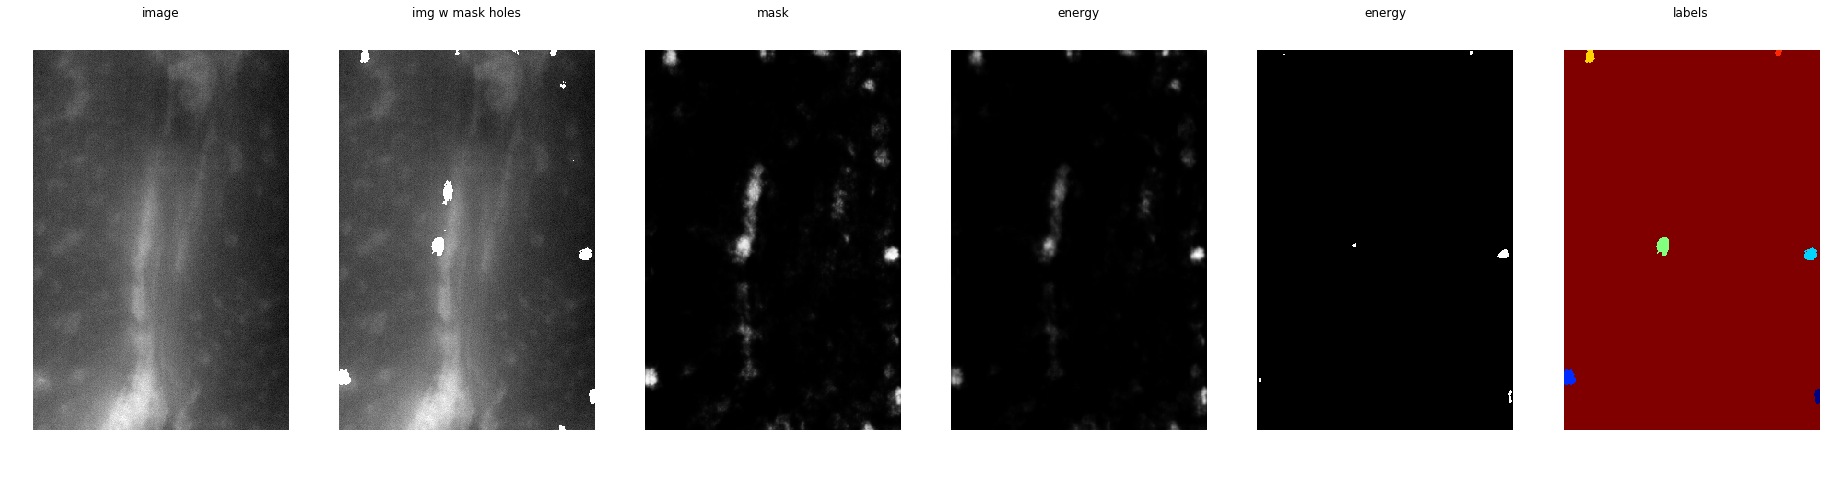

Идея в том, чтобы CNN учила две вещи — единичные вектора указывающие на границы и уровень энергии (высота гор)

На практике, если вы просто примените WT (Watershed Transform), скорее всего у вас получится слишком парцеллярная сегментация. Интуиция, лежащая за DWT, такая — надо научить CNN находить "горный ландшафт" за нас.

Для меня лучшим пост процессингом (функция energy_baseline по ссылке) был такой алгоритм действий:

- Суммируем предсказанную маску и три уровня предсказанных масок с эрозией;

- Применяем порог в 0.4, чтобы разделить центры клеток;

- Используем найденные центры в качестве маркеров для заливки;

- Используем расстояние до границы масок в качестве меры "высоты ландшафта";

Один из лучших примеров — сетка смогла четко разделить слипшиеся ядра

Выученные градиенты не подходят для использования в качестве водоразделов